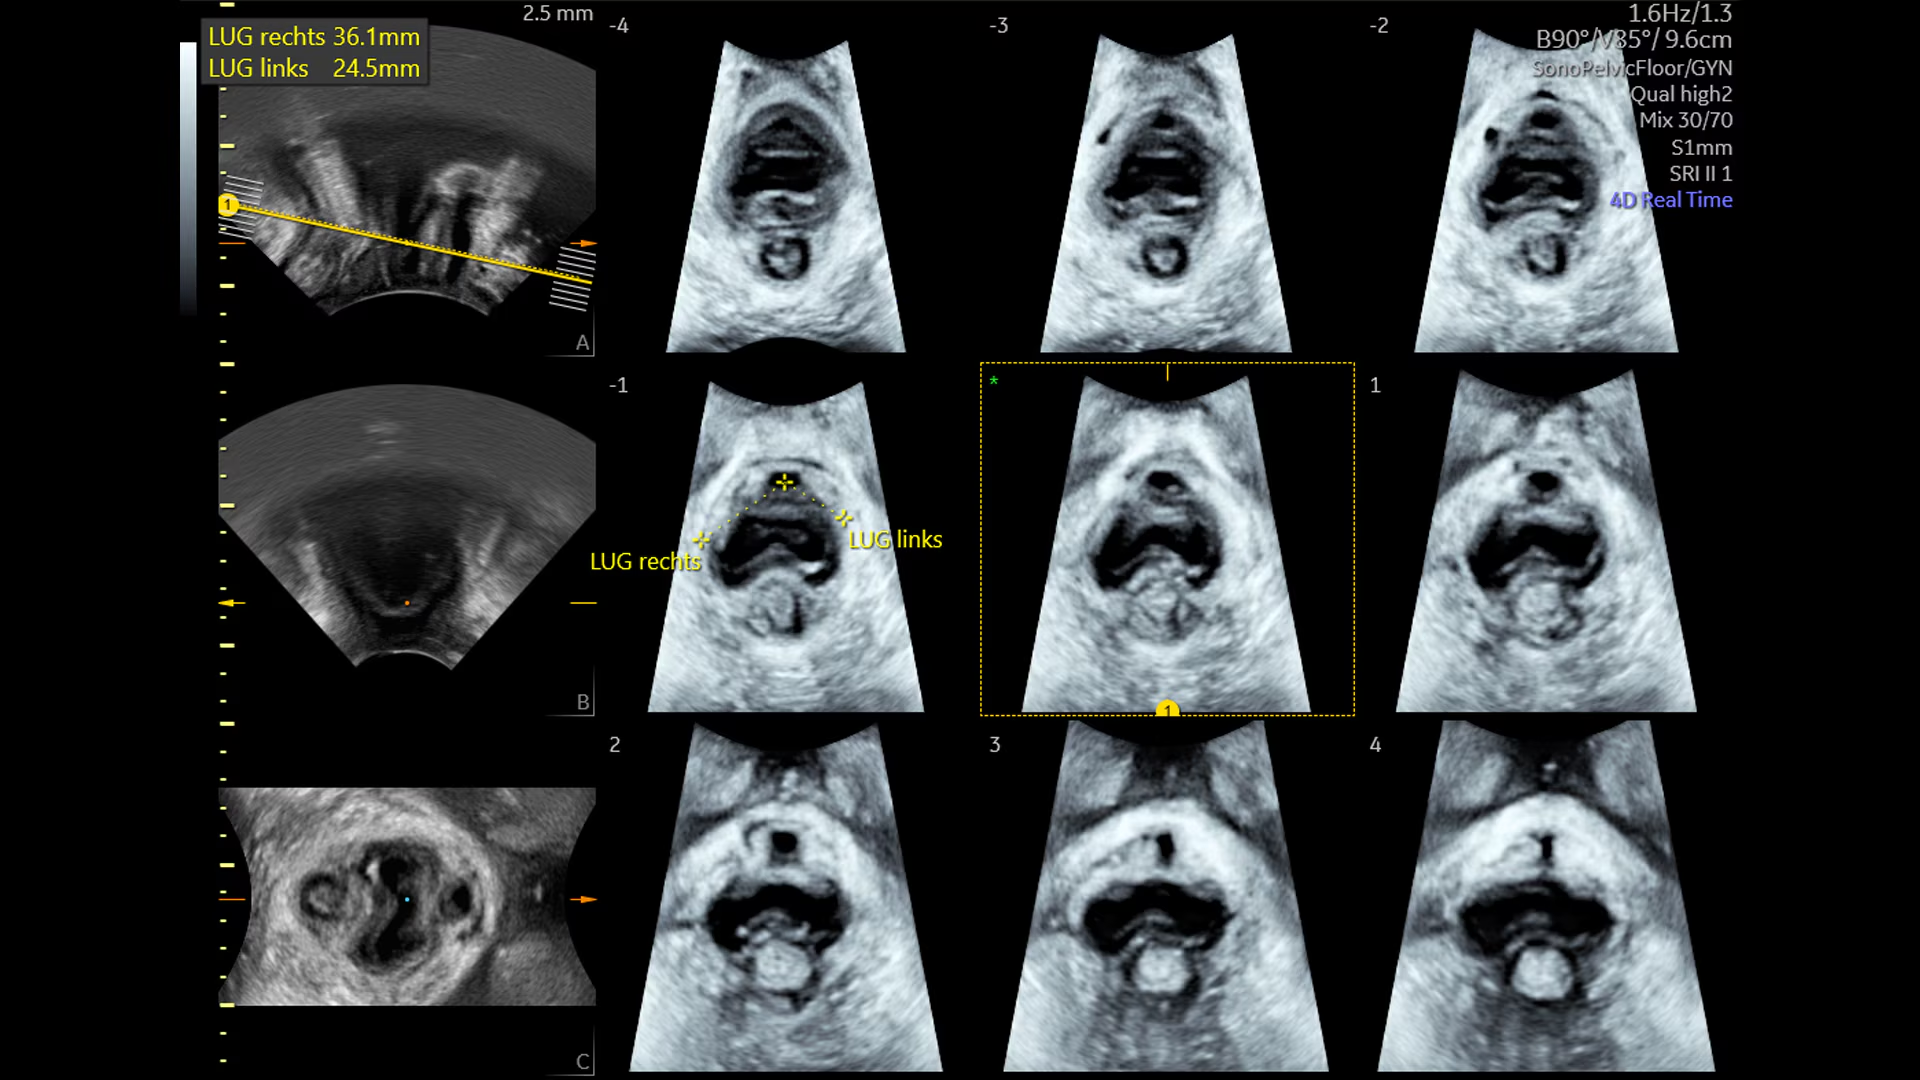

SonoPelvicFloor оптимизирует исследование тазового дна: система автоматически выравнивает плоскости, измеряет углы и расстояния, создавая воспроизводимые результаты при каждом обследовании.

SonoPelvicFloor автоматически выравнивает плоскости и измеряет ключевые параметры, позволяя объективно оценивать функцию тазового дна и динамику его изменений после родов или хирургического вмешательства